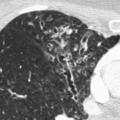

Seul un scanner thoracique haute résolution confirme le diagnostic anatomique : augmentation permanente et irréversible du calibre des bronches sous-segmentaires, cylindriques, variqueuses ou kystiques, localisées à un lobe ou diffuses. On élimine une autre cause de toux chronique comme un cancer bronchique. Toux, expectoration, infections bronchiques répétées + bronchectasies au scanner définissent le syndrome bronchectasique.